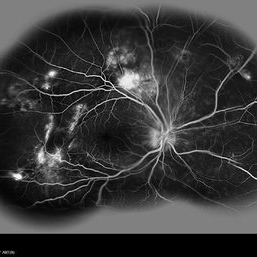

Multifocal Exudative Detachments Due to VKH

May 14 2014 by Avris Romario Diparaja Siahaan

FA (composite Image) a 38-year-old man with multifocal CSR and inferior exudative retinal detachment on both eyes (Harada Syndrome).

Photographer: Avris Romario Diparaja Siahaan, Klinik Mata Nusantara

Imaging device: Heidelberg HRA + OCT Spectralis

Condition/keywords: multifocal central serous chorioretinopathy (CSCR)